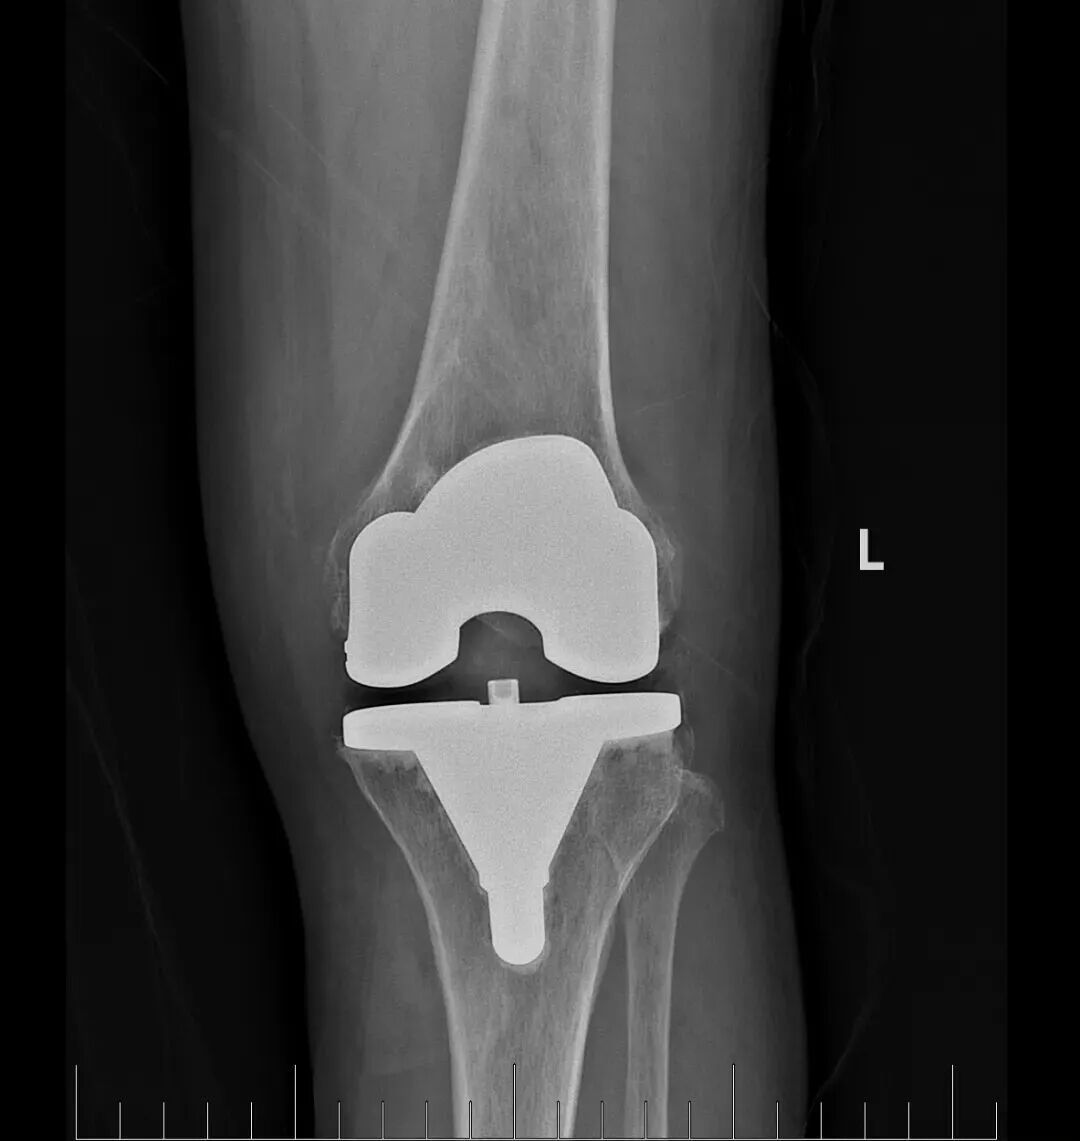

在充分的术前准备基础上,骨科蔡志荣主任带领团队,为李女士实施了左侧全膝关节置换术。团队凭借精湛的操作技术,精准完成了假体植入与软组织平衡,术中出血量仅30毫升,无需输血,患者生命体征平稳。得益于“快速康复外科”理念的应用,李女士在术后第二天就能在助行器辅助下站立并行走。恢复速度远超传统关节置换术后的康复进程,患者及家属对治疗效果赞不绝口。